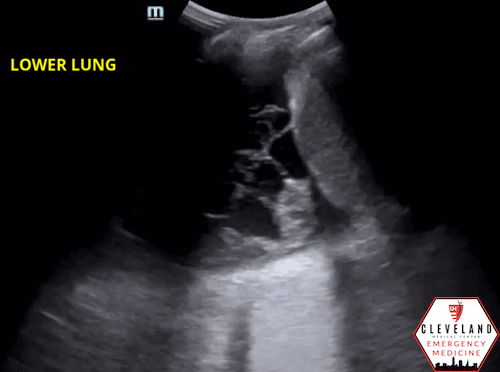

Lung ultrasound revealed consolidation throughout the majority of the left lung along with a complex-appearing/loculated pleural effusion in the lung base. The right lung was unremarkable.

Consolidation

• As fluid or cells fill the alveoli, areas of consolidation start to replace normal lung. Smaller consolidations may appear as focal hypoechoic areas just below the pleural line, while larger consolidations tend to develop an organ-like appearance (“hepatization”), as seen in the majority of the lung in the case above . Air that gets trapped in the fluid-filled consolidation may be visualized as bright echoes; if they move with respiration, it is a dynamic air bronchogram which is considered pathognomonic for pneumonia. Irregular borders are often seen. [15-16].